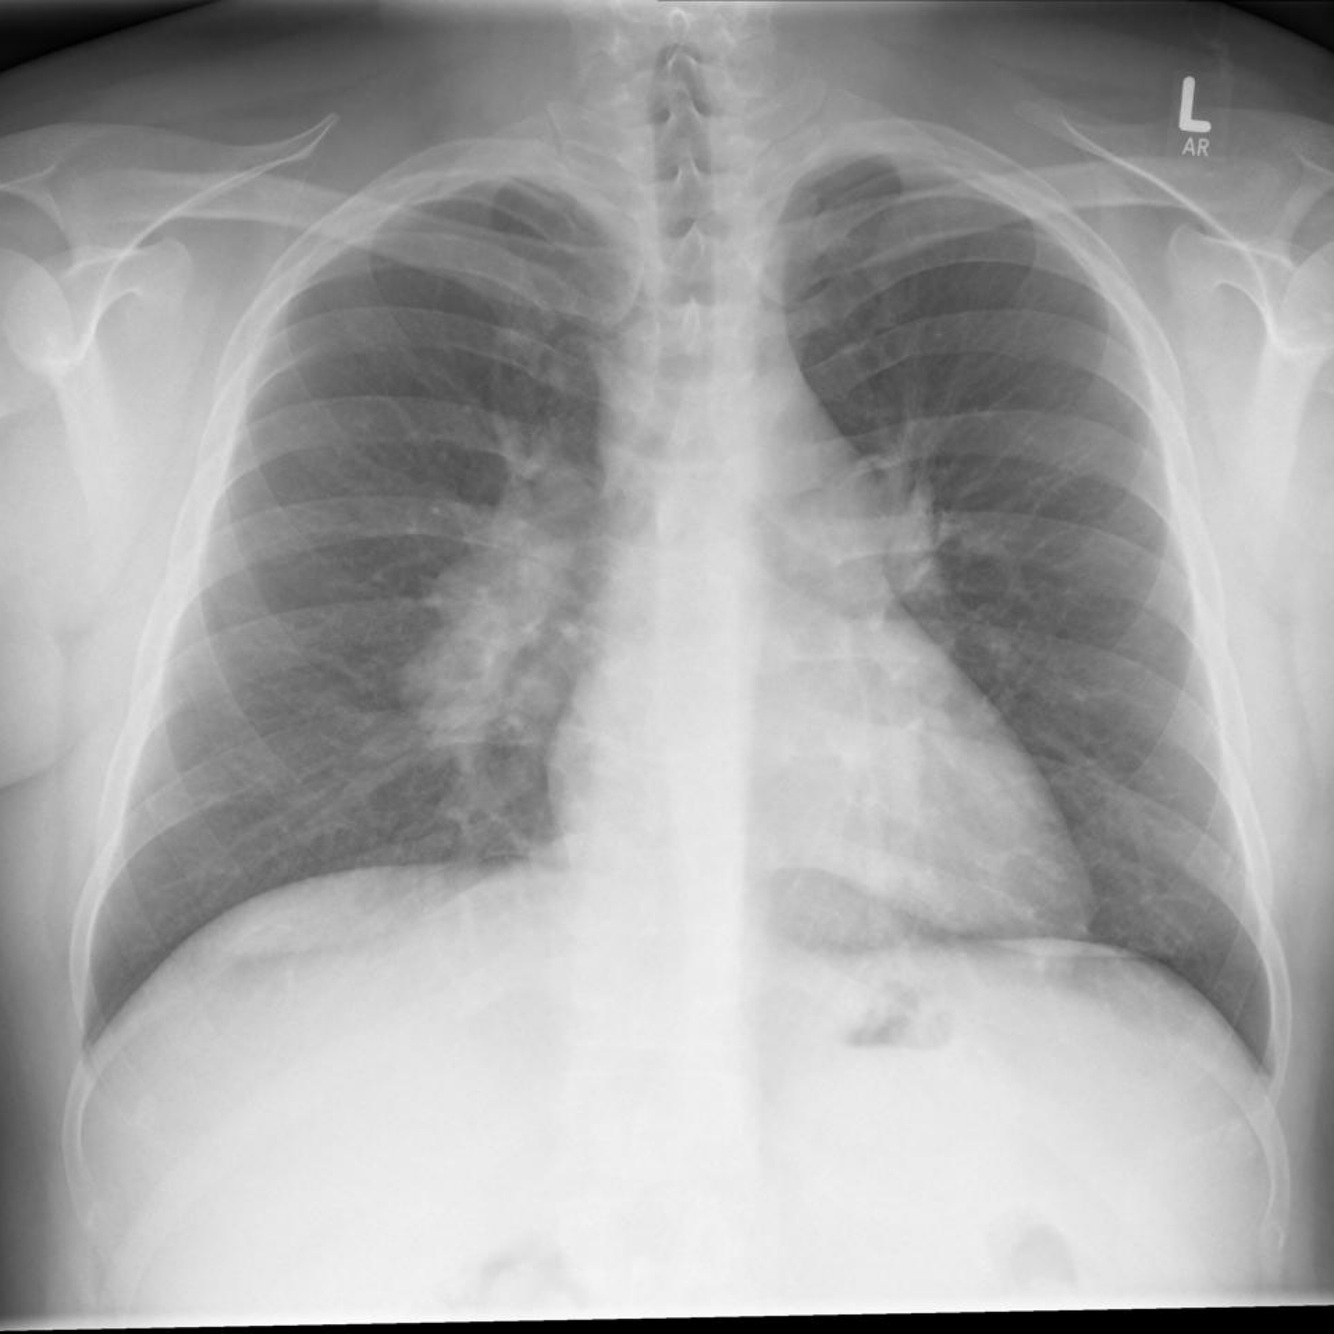

What does this CXR show?

Bilateral hilar lymphadenopathy as in sarcoidosis